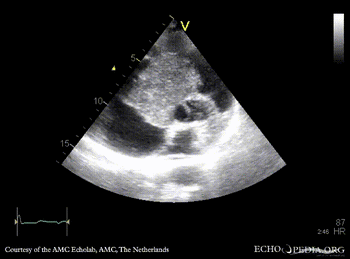

| Giant myxoma in right atrium

| PLAX: giant mobile myxoma in right atrium

PLAX